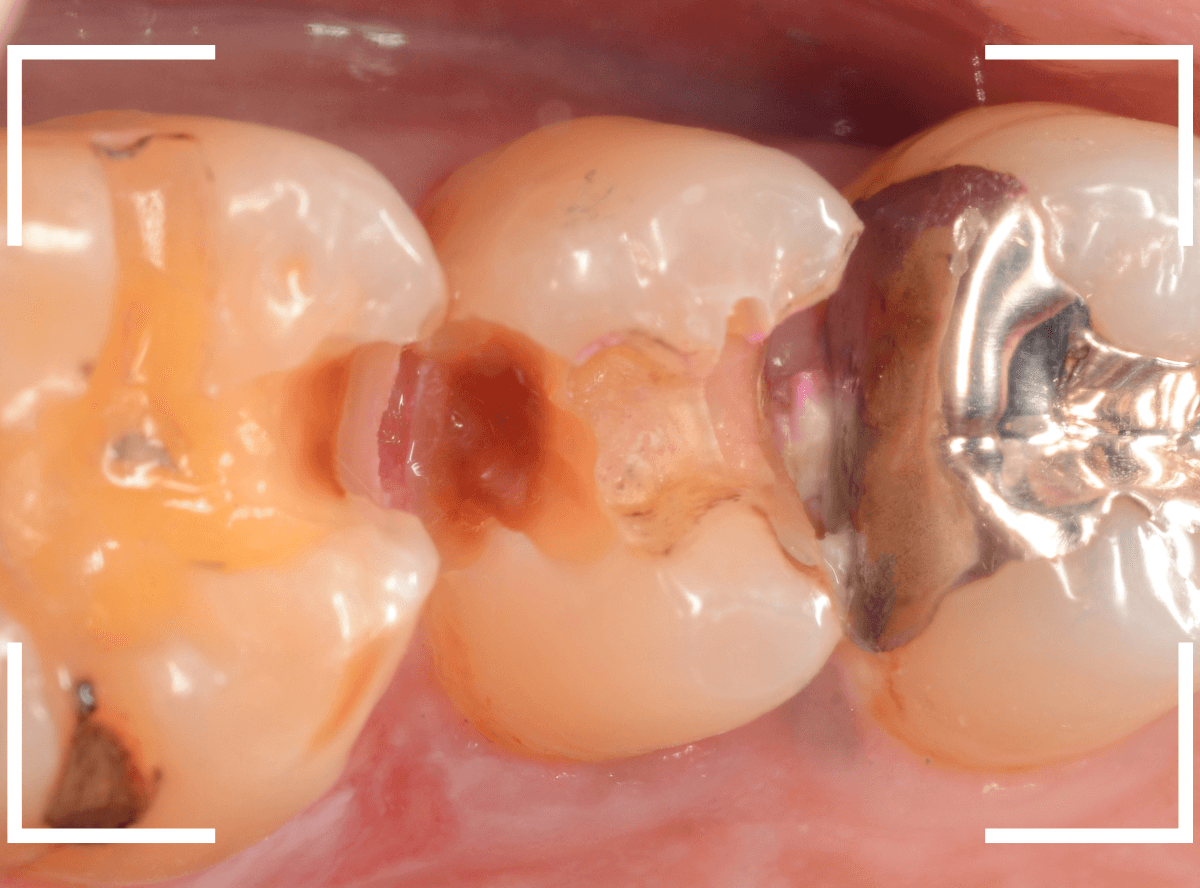

Case.23 歯のすきまから両側が大きな虫歯

「下の奥歯が痛む」という訴えで来院された患者さんのケースです。

目視でも、手前の奥歯がかけていて、中で虫歯が広がってるであろうことは予想できます。

ピンセットで歯を叩いてみても、手前の奥歯が痛むようです。

レントゲン写真で確認します。

青い線が神経、赤い線が虫歯の範囲です。

奥歯の方がより深い虫歯に見えますが、再度打診で確認したところ、やはり手前の奥歯が痛むそうです。

状況から、まず手前の奥歯から治療となりました。

麻酔をして、手前の奥歯のレジンを慎重に外します。

前に虫歯の治療をした時点で、神経スレスレの状態でしたので、削りすぎないように慎重にレジンを外さなければいけません。

レジンを外して、う蝕検知液で確認します。

レジンの中で虫歯が進行していたのがわかります。

慎重に全ての虫歯を除去しました。

何とか、神経が露出せずに済んでいます。

お薬をつめて、セメントで蓋をして経過観察します。

後日、状況を確認したところ、虫歯処置した後も、手前の奥歯が痛むとの事でした。

「我慢できないほどでもない」との事でしたので、引き続き経過観察しつつ、奥歯の治療を治療する事になりました。

奥歯は、レントゲンで見た通り、少し歯を削るとすぐに虫歯の穴が出てきました。

こちらは、ある程度虫歯を取ったところで染め出してみると真っ赤です。

ですが、何とか神経に達する前に、全ての虫歯を除去できました。

神経の治療が必要かと思っていたので、その点は幸運でした。

奥歯もお薬をつめて、セメントで蓋をして経過観察です。

何とか神経を取らずに済ませたいですが、どうなる事か・・・。